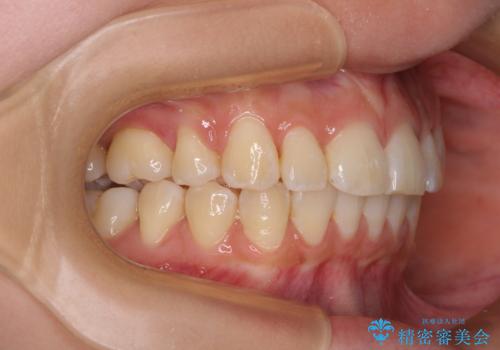

- 口を閉じたときに唇の間から飛び出してくる前歯を気にして来院された患者様です。

骨格的に上顎骨が前方位にあるため、左右の第一小臼歯を抜歯し、ワイヤー装置にて咬み合わせを整えていくこととしました。

前歯の突出感が改善されるだけでなく、奥歯の咬み合わせも改善され、食いしばりをしにくい状態に仕上げることができました。